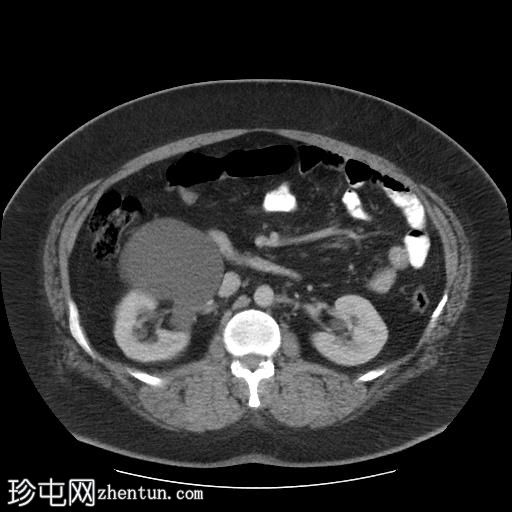

轴位肾实质期

右肾集合系统完全重复。上肾集合系统的输尿管异位开口于前列腺尿道,导致上游集合系统显著扩张。这引起肾实质的慢性改变,包括上肾组织变薄和上肾盏排尿功能障碍。

相反,右肾下肾集合系统的输尿管位置正常,无扩张或结石迹象。

左肾和输尿管外观正常。

右肾重复畸形伴异位输尿管的CT表现。异位输尿管是一种先天性异常,指输尿管在异常位置开口于膀胱。